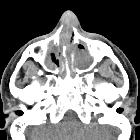

CT

- non-contrast CT

- sinonasal mucosal thickening +/- air-fluid levels +/- soft tissue nodules

- bony/cartilaginous erosions, in particular, affecting lamina papyracea, nasal septum, and lateral nasal cavity wall +/- perforation